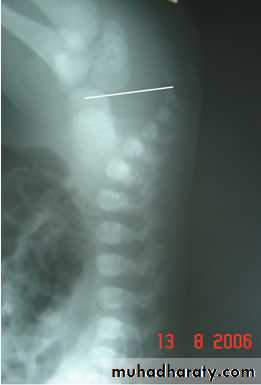

Radiology

Determined:1-relation of rectum to sphincter muscle.

2-associated anomalies.

1-x-ray of the spine and chest (sacral , VATER).

2-Lateral invertogram ( pubococcegeal line) 18-24hr.after birth.

-gas shadow above this line suggest high type.

- gas shadow below suggest low type.

3-lateral decubitus X-ray.

4-M.R.I.